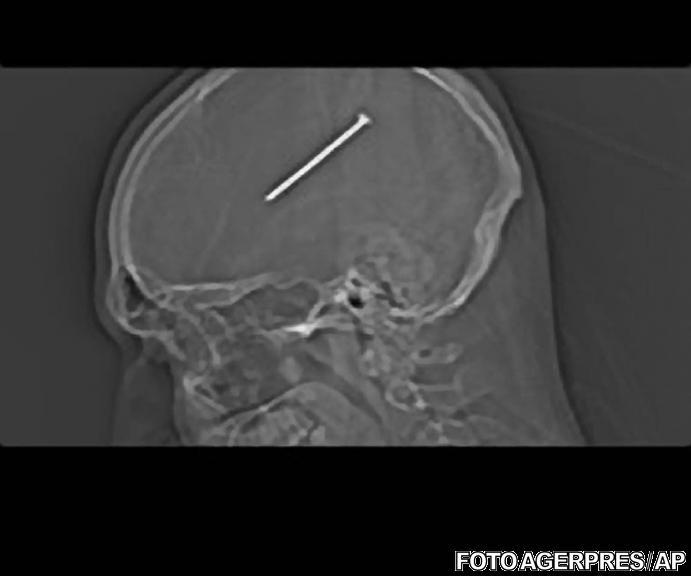

VIDEO Doctorii au reusit sa inlature un cui de 8.25 cm din creierul unui american, care s-a impuscat din greseala

Doctorii din Statele Unite au reusit sa inlature un cui lung de 8.25 de cm din creierul unui american de 32 de ani, care s-a impuscat din greseala in cap cu un pistol pneumatic de batut cuie, in timp ce facea reparatii la locuinta, transmite SkyNews. Dante Autullo se reface bine dupa interventia chirurgicala la care a fost supus.

O radiografie realizata de medici a indicat faptul ca barbatul avea infipt in creier un cui de 8.25 cm lungime.

Doctorii au declarat ca cuiul tras de Autullo a ratat cu doar cativa milimetri portiunea din creier ce controleaza functiile motorii, astfel explicandu-se faptul ca barbatul a continuat sa munceasca si sa vorbeasca fara probleme.